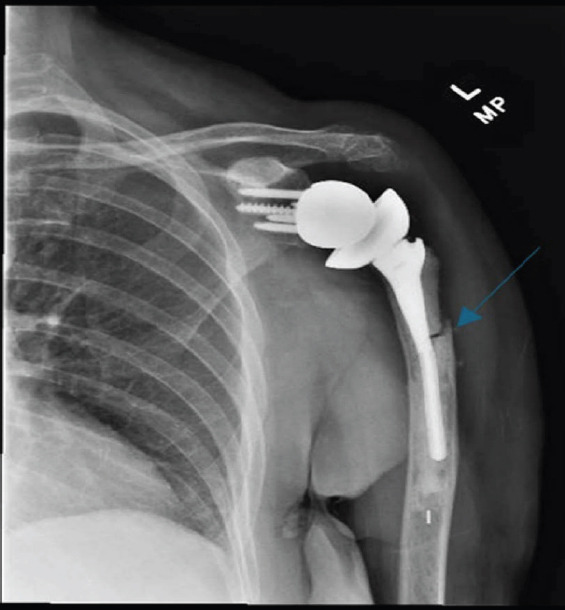

Introduction: Reverse total shoulder arthroplasty (RTSA) is increasingly performed, with a corresponding rise in associated complications such as periprosthetic fractures. Although implant failure and loosening are well documented, deformation of a humeral stem without loosening has not been previously reported.

Case report: A 77-year-old woman, 9 years after an RTSA, presented with left shoulder pain after a fall. Initial radiographs revealed a transverse periprosthetic proximal diaphyseal fracture and a deformed humeral component. She was treated nonoperatively with range-of-motion exercises and pain management. One year later, radiographs confirmed fracture healing, and the patient had no pain and had regained full motion.

Conclusion: This is the first reported case of deformation of a humeral stem in a shoulder arthroplasty. Nonoperative management was successful for fracture healing.